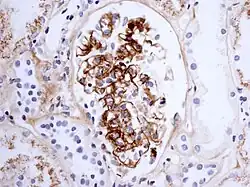

La maladie se caractérise par un dépôt d'immunoglobuline de type A1 dans les parois des vaisseaux et dans le tissu rénal (mésangium).

- enfin, une atteinte rénale glomérulaire d'intensité variable dans environ 40 % des cas, caractérisée en général par une protéinurie, une hématurie, en général sans insuffisance rénale aiguë ;